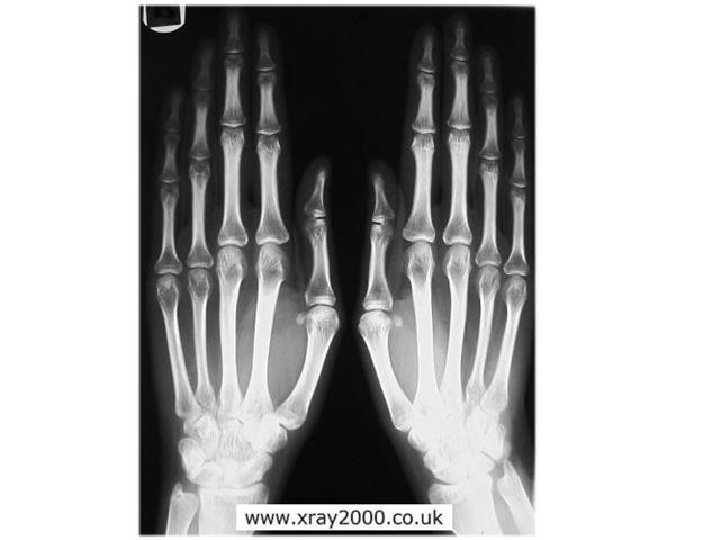

Bones of the Hand

Carpels Bones of the Hand

Metacarpels Carpels Bones of the Hand

Phalanges Metacarpels Carpels Bones of the Hand